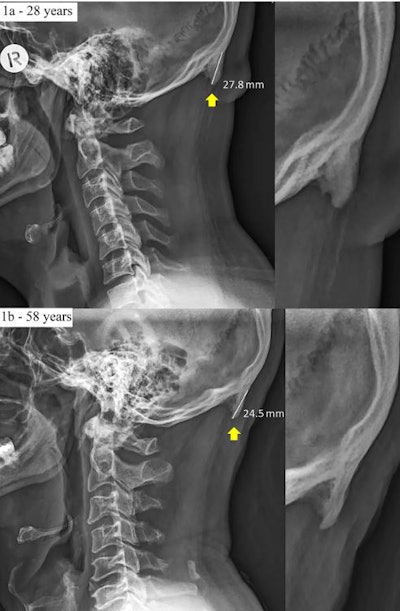

But the example that has been getting the most attention concerned the growth of "horns" in young adults who are heavy users of smartphones. The BBC article describes a paper published February 20, 2018, in Nature's Scientific Reports in which Australian researchers discovered a higher prevalence of external occipital protuberances in the skulls of young adults -- bony outgrowths that they documented with radiography.

In their 2018 paper, David Shahar, PhD, and Mark Sayers, PhD, of the University of the Sunshine Coast examined the prevalence of enlarged external occipital protuberance (larger than 10 mm) in a population of 1,200 individuals ages 18 to 86. They found that male sex, younger age, and a higher degree of forward head protraction were positive links to the development of the protuberances.